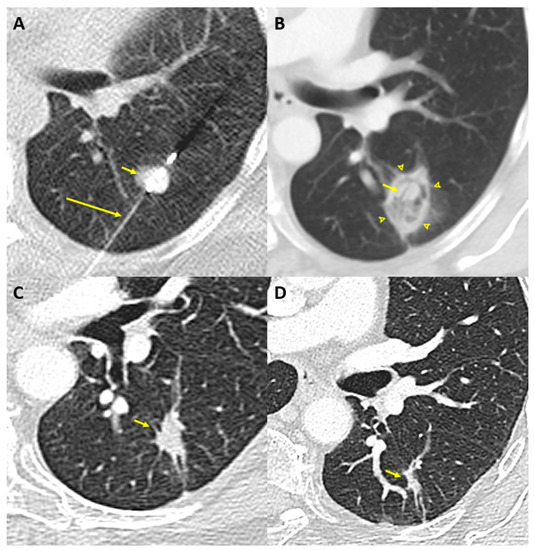

Based on the results of this review, previously published recommendations on lung metastases by Handy et al. [30] and Najafi et al. [104], and the recent Society of Thoracic Surgeons webinar on pulmonary metastasectomy [105], we propose an algorithm to help choose the optimal local ablation therapy among surgery, SBRT and TA, illustrated in Figure 2.

Figure 2.

Proposed decision algorithm for local ablation therapy of oligometastatic non-small cell lung carcinoma.